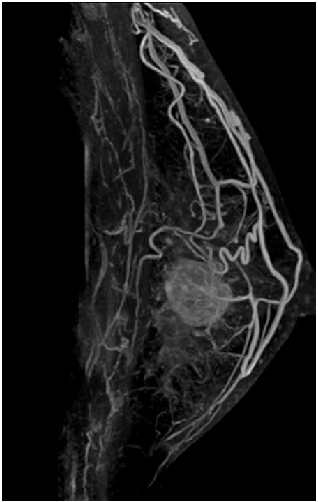

乳腺成像方向

高分辨率图像让肿瘤与正常乳腺组织更容易分辨,通过动态增强、波普、时间信号强度曲线及ADC值评价肿瘤良恶性符合率更高,其敏感度和准确度明显高于其他检查方法。